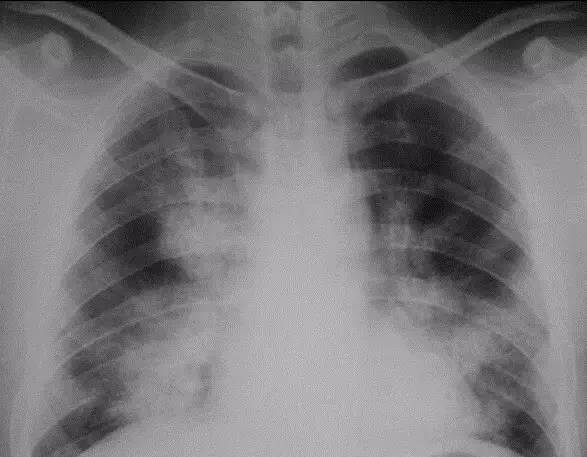

二 X线胸片表现

X线胸片是诊断本病的初级筛选方法,表现为与病理特征一致的两肺广泛性肺泡腔填塞,两肺广泛肺泡实变,显示为散在的粟粒状或颗粒状阴影,轮廓模糊,随病变进展融合形成不规则、斑片状、轮廓模糊的阴影,双肺病变广泛且较对称,部分病例在融合的阴影中伴有小点的透亮区,后者代表未实变而呈代偿性肺气肿的肺泡。不少病例病变分布以中央部位较多,自肺门向外放射,形成蝶翼征,并可见支气管充气征,类似肺水肿,但无心脏增大表现(图1)。

(图1) 医学百科网 | YxBaike.Com

部分病例经过数月或数年阴影可逐渐消失,这可能反映了疾病的一种自然病程。致密的实变影,特别是伴有空洞形成的,提示合并肺炎。